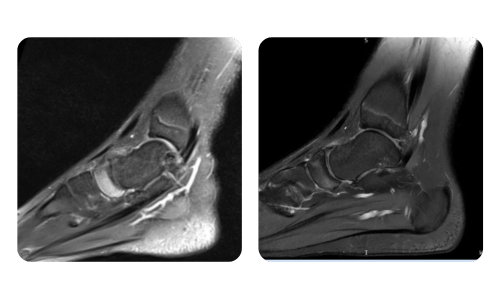

The progress of our patients, measured before and after hyperbaric therapy, reflects the efficiency and positive impact of the treatment. Discover documented results of hyperbaric therapy at Hyperbarium Oradea clinic, based on clinical evaluations and objective data that highlight significant improvements in various conditions.